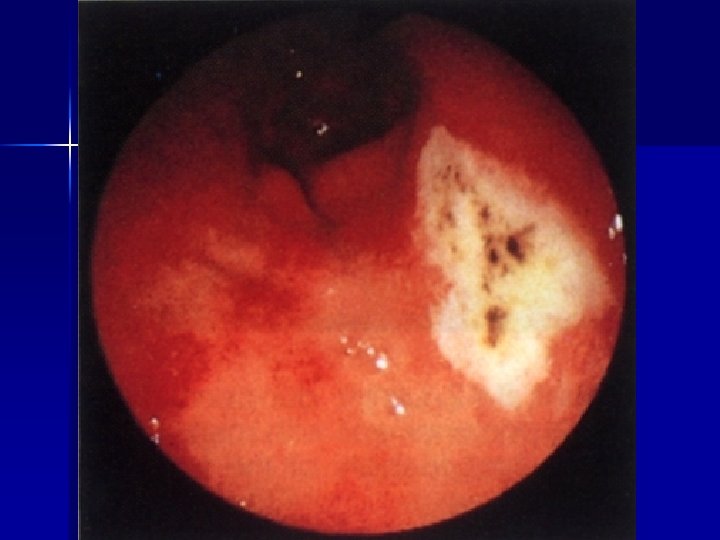

ENDOSCOPIA Lesioni del basso esofago n Patologia gastroduodenale(gastrite, ulcere, ernia iatale, corpi estranei) n Patologia rettocolica (colite ulcerosa, aspecifica, allergica, m. di Chronn) n